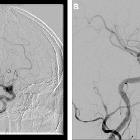

infectious pseudoaneurism of the carotid bifurcation. Arteriography showing the pseudoaneurysm.

Acute

infectious pseudoaneurism of the carotid bifurcation. Contrast flow inside the pseudoaneurysm.